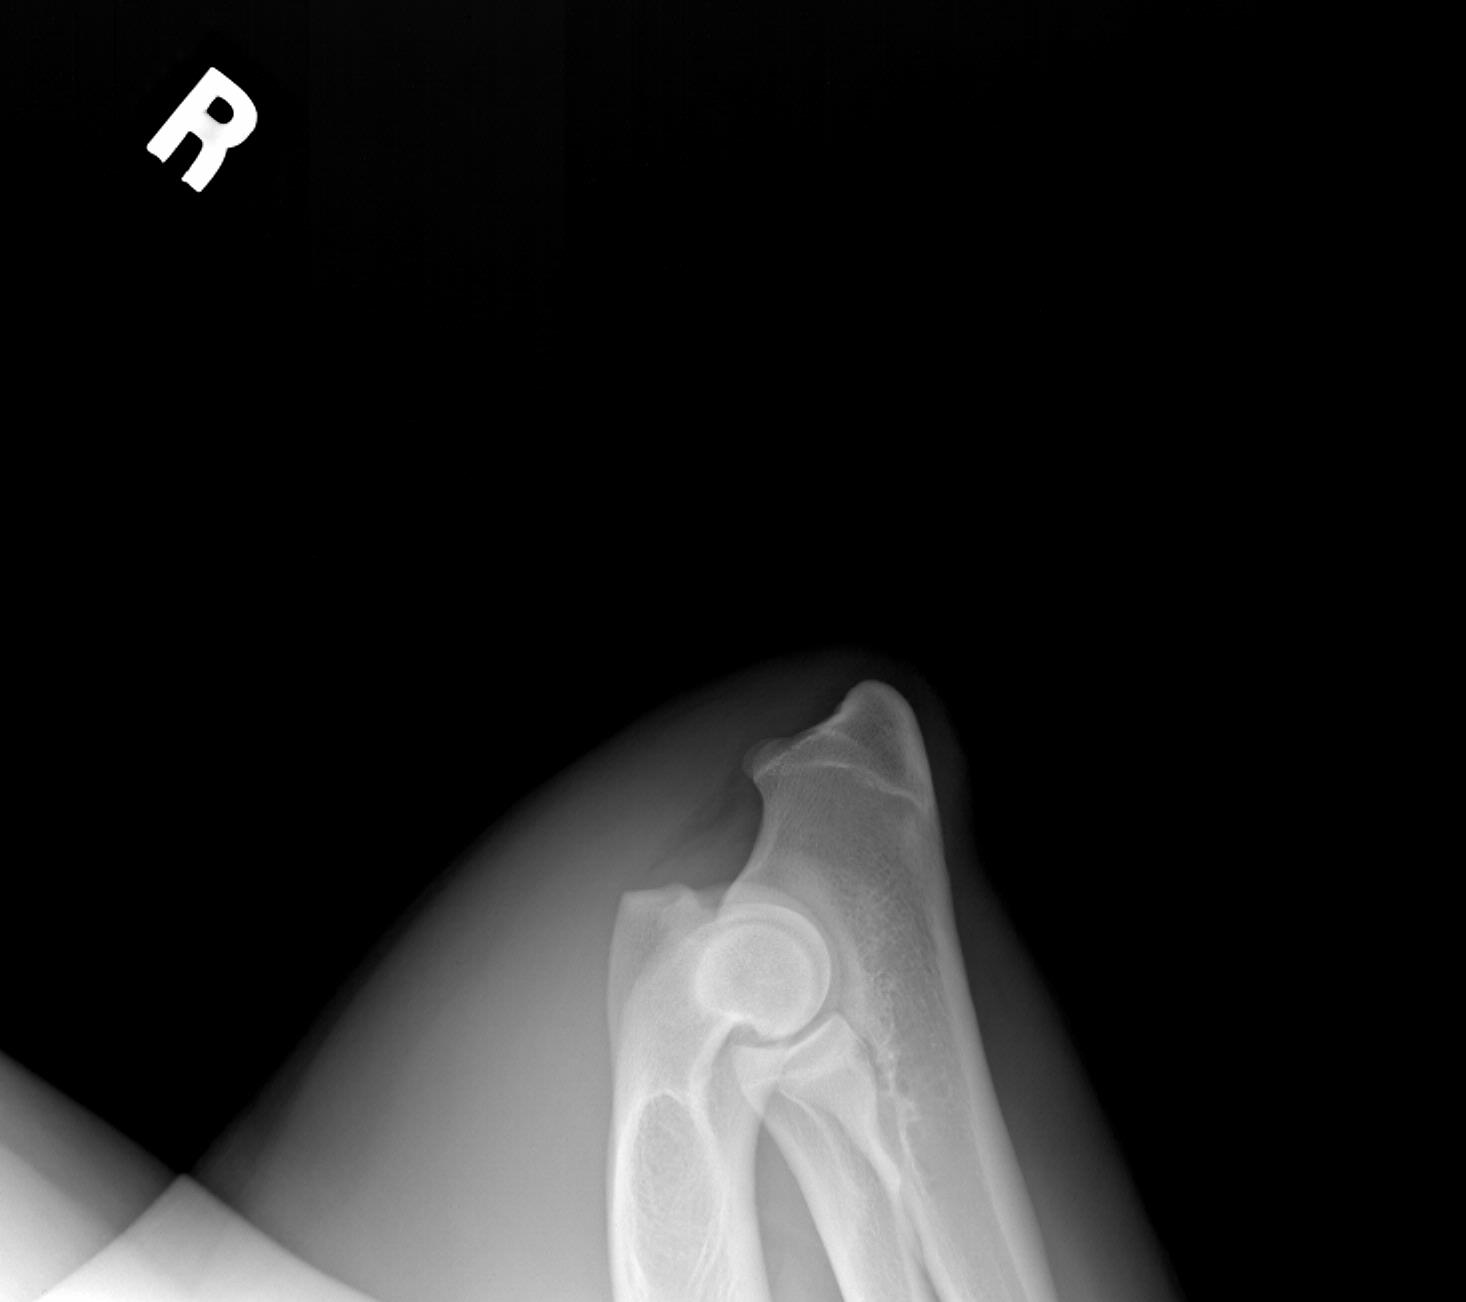

Coal's hip and elbow radiographs, taken his second birthday, 12/16/09. Dr. Peter Brown of Chuckanut Valley Vet Clinic, who has read for OFA, said: "The hips look excellent. The elbows are so good, the edges are so clean and sharp, that I will use these pictures when showing an example of normal elbows." We were excited to see that OFA agreed! :)